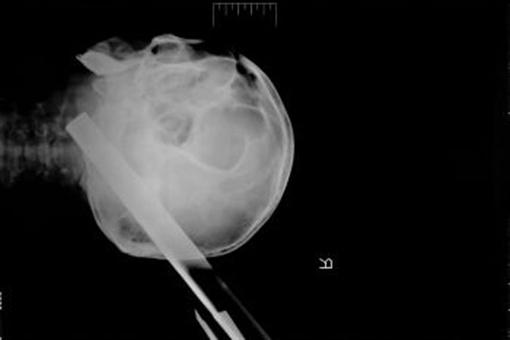

Табурет буквально торчал из головы больного - одна из ножек пробила череп в области затылка, пройдя на 11 сантиметров до самого его основания, сквозь вещество головного мозга. Пациента экстренно увезли в операционную, где дежурная бригада нейрохирургов с величайшей осторожностью извлекла инородное тело из головы мужчины.

- После удаления столь массивного предмета во время операции у больного не возникло даже ожидаемого кровотечения, - рассказывают нейрохирурги Красноярской краевой клинической больницы. - Удивительно, но факт: пациент остался жив. Мужчина провел две недели в нейрореанимации в тяжелом состоянии, где, на фоне интенсивной терапии его состояние стабилизировалось.